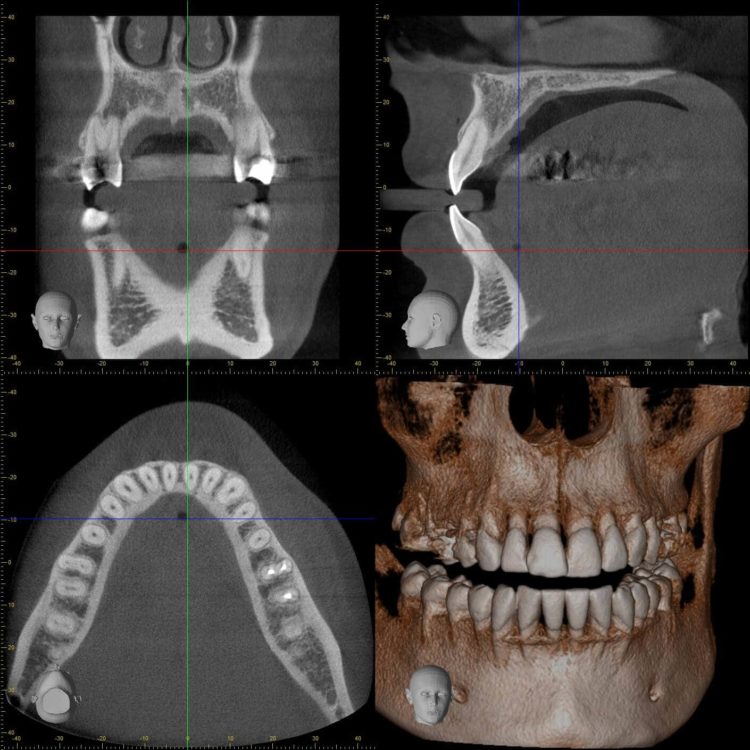

L’extraction des dents de sagesse se déroule sur un fauteuil dentaire dans des conditions stériles pour limiter les risques de transmission infectieuse. Dans les cas compliqué, une radiographie 3D (tomographie volumétrique digitalisée) peut être réalisée préalablement pour faciliter le travail du chirurgien et limiter les risques de l’intervention.